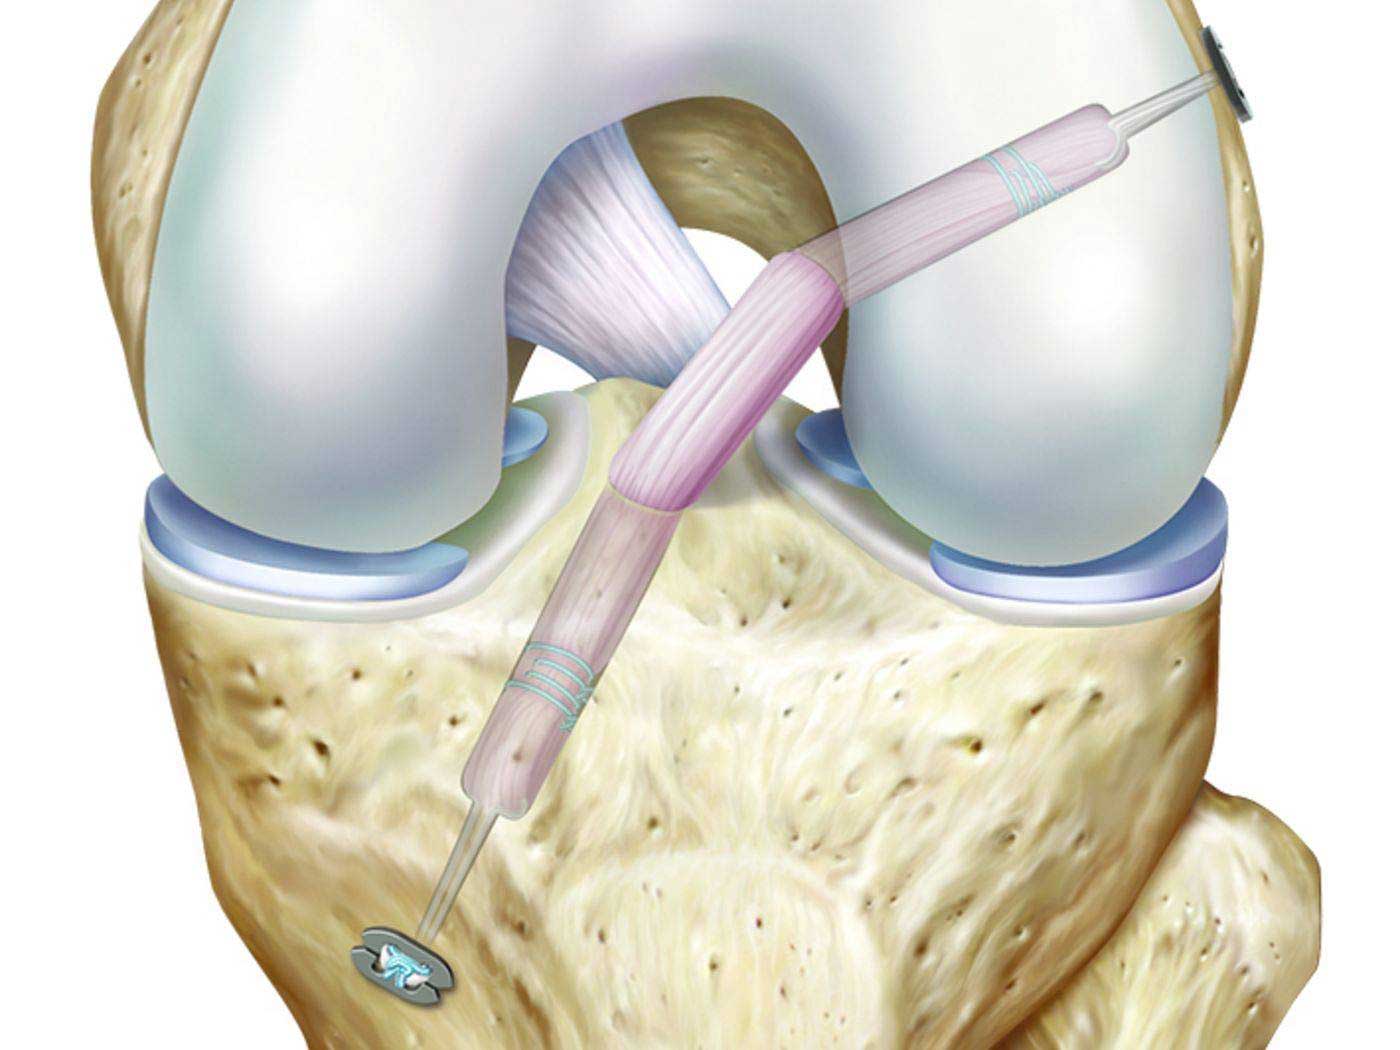

A bone graft is a surgical procedure used to repair fractures or tears in bones by fixing the damaged bone pieces using plates or surgical screws, usually in the form of a patch on the bone’s surface. Bone grafts help restore bone stability, promote healing, and are used in a variety of cases that require surgical bone fixation, including:

- Ligament and tendon tears

- Solid ligament fractures

- Bone grafting is used to help stimulate the healing of bones in areas where natural healing is slow or challenging. It can create an optimal environment for fractured or weak bones to recover and heal.

- Bone grafting can enhance the stability of fractured or cracked bones by fixing bone fragments.

- In some cases, autografts can be used to stabilize damaged or fractured bones, providing additional support.